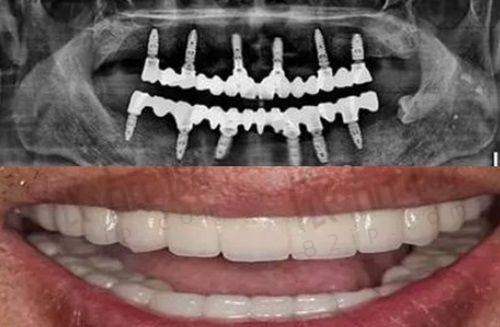

爱尔创全瓷牙是一种高品质的牙齿修复材料,它采用了精良的全瓷技术,具有美观、耐用、生物相容性好等优点。与传统的金属烤瓷牙相比,爱尔创全瓷牙不含金属成分,不会对牙龈造成刺激和过敏反应,能够更好地保护口腔健康。

在美观方面,爱尔创全瓷牙的颜色和透明度与天然牙齿非常接近,几乎可以达到以假乱真的成效。它能够根据患者的牙齿颜色和形态进行个性化定制,使修复后的牙齿与周围的牙齿更加协调自然,提升整体的美观度。

在耐用性方面,爱尔创全瓷牙具有较高的强度和硬度,能够承受较大的咀嚼压力,不易破裂和磨损。它的使用寿命较长,一般可以达到10年以上,为患者提供了长期的牙齿修复保护。

此外,爱尔创全瓷牙还具有良好的生物相容性,不会对人体产生任何不良影响。它能够与口腔组织良好地融合,减少了牙龈炎症和牙周疾病的发生风险,为患者的口腔健康提供了有力的保护。